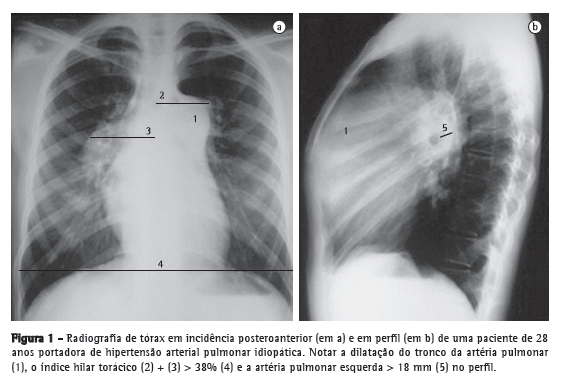

Contudo, a fração de ejeção e os volumes do VD não podem ser calculados usando as equações matemáticas normalmente aplicadas ao estudo do VE. Por esse motivo, diversos parâmetros ecocardiográficos foram desenvolvidos para avaliar a função do VD e a condição hemodinâmica da artéria pulmonar. O método mais praticado baseia-se na identificação da tricuspid regurgitation (TR, regurgitação tricúspide). A medida da TR fornece uma estimativa do gradiente pressórico entre as câmaras cardíacas direitas. Os primeiros trabalhos datam de meados da década de 80,(9,10) nos quais fora empregada a técnica de Doppler de onda contínua. A técnica consiste em medir a velocidade de pico da regurgitação tricúspide (VTR), que oferece uma estimativa do fluxo regurgitante do VD para o átrio direito (Figura 3). Aplicando-se a equação simplificada de Bernoulli (∆P = 4 × VTR2), é possível converter a medida de fluxo em uma estimativa de pressão. Adicionando a esse gradiente pressórico uma estimativa da pressão de átrio direito, obtém-se o valor da pressão sistólica de pico do VD (PsVD), uma aproximação da pressão sistólica de artéria pulmonar (PsAP), desde que ausentes obstruções na via de saída do VD. O resultado de PsVD > 35-40 mmHg é sugestivo de HP.(10) Na presença de fluxo regurgitante baixo, a estimativa da PsVD torna-se menos sensível, porquanto a intensidade de sinal de eco é baixa, o que pode subestimar os valores de pressão. Mas situações de TR muito intensa também podem subestimar as medidas de pressão porque resultam em equalização das pressões entre o átrio direito e o VD, dificultando o sinal ao Doppler. Por outro lado, o método também pode superestimar os valores de PsVD.

Outros sinais ecocardiográficos, como aumento das câmaras cardíacas direitas, derrame pericárdico, disfunção de VD, movimentação paradoxal do septo interventricular e redução dos volumes de enchimento do VE, também corroboram a presença de HP (Figura 3).(18) Guardadas suas limitações e bem avaliados e interpretados à luz do contexto clínico, todos esses parâmetros podem ter utilidade no diagnóstico e no seguimento de pacientes com HP.